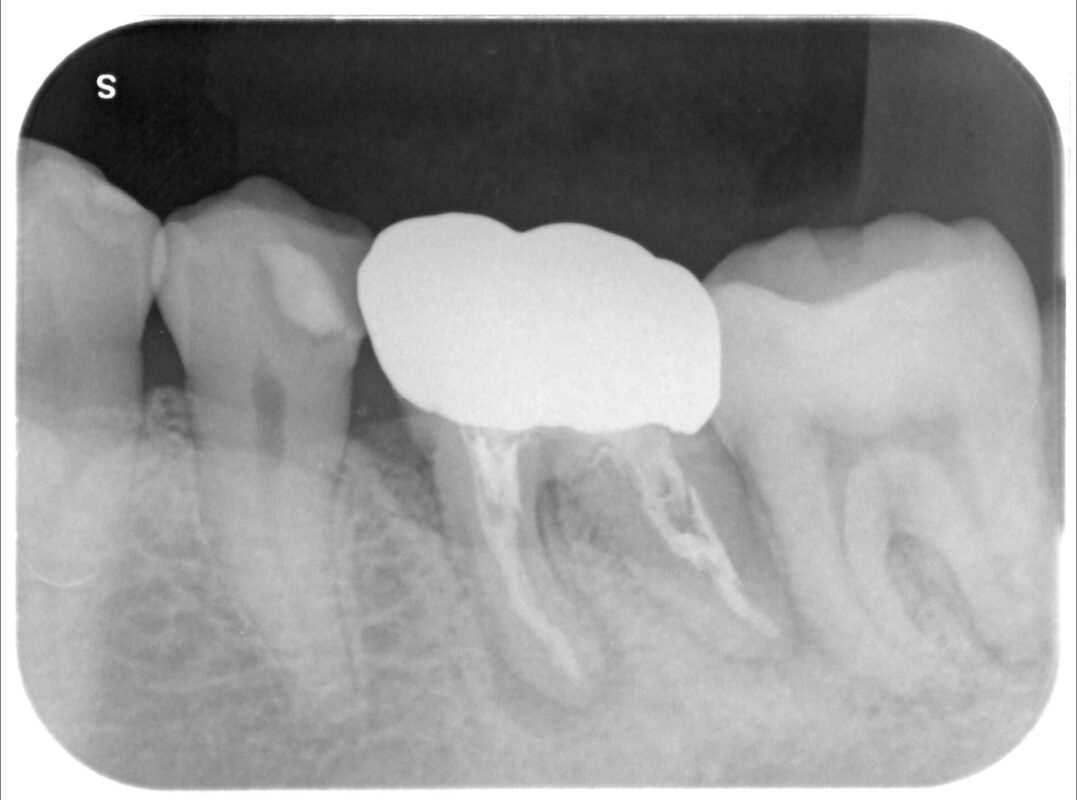

術前

確かに銀歯部分は破折しているようです。

根管治療の精度も疑問ですが。

また、その右側の歯牙も骨の吸収著しいです。